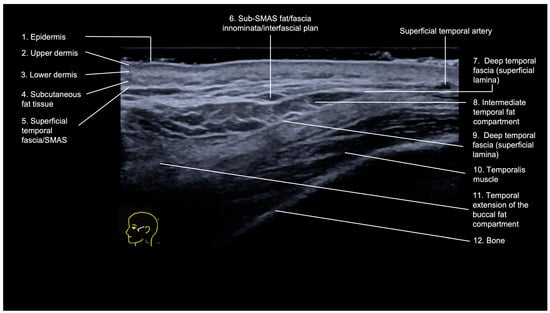

- Epidermis: hyperechoic line.

- Upper dermis: hypoechoic homogeneous layer.

- Lower dermis: usually more echogenic layer than the upper dermis.

- Subcutaneous fat tissue: a hypoechoic layer composed of fat lobules and hyperechoic septae.

- Superficial temporal fascia/Superficial musculoaponeurotic system (SMAS): linear hyperechoic layers enveloping the superficial temporal artery and vein.

- Sub-SMAS fat: also called innominate fascia, it is a hypoechoic layer composed of loose connective tissue and fat lobules. This is the interfascial plane.

- Superficial lamina of the deep temporal fascia: a hyperechoic line, which is juxtaposed to the intermediate temporal fat compartment.

- Intermediate fat compartment (loose areolar tissue): a hypoechoic triangular layer composed of fat lobules and hyperechoic septae. The middle temporal vein can be encountered in this layer.

- Deep lamina of the deep temporal fascia: a hyperechoic line, which is deep to the intermediate temporal fat compartment.

- Temporal muscle: a large hypoechoic structure above the bone, where the anterior and posterior deep temporal arteries are located.

- Temporal extension of the buccal fat compartment: a hypoechoic fat compartment adjacent to the lateral orbital rim, connected to the buccal fat pat. Easily recognized when patient is asked to open and close the mouth, this fat pad can be found under the deep lamina of the deep temporal fascia.

- Bone: a thin hyperechoic line with acoustic shadowing.